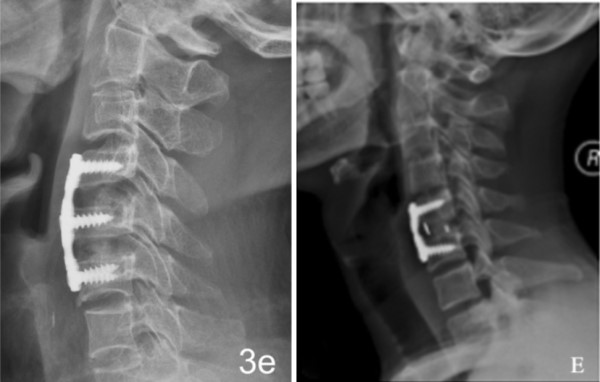

Product Introduction

产品介绍